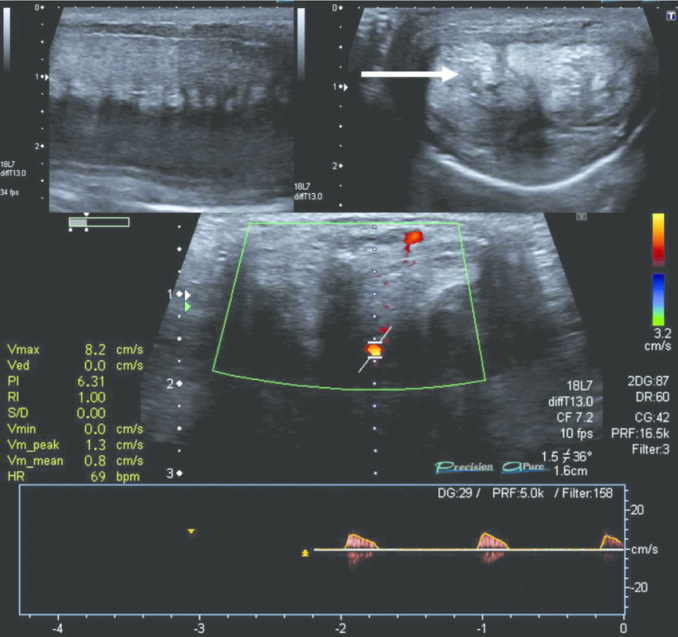

Badanie ultrasonograficzne Adama